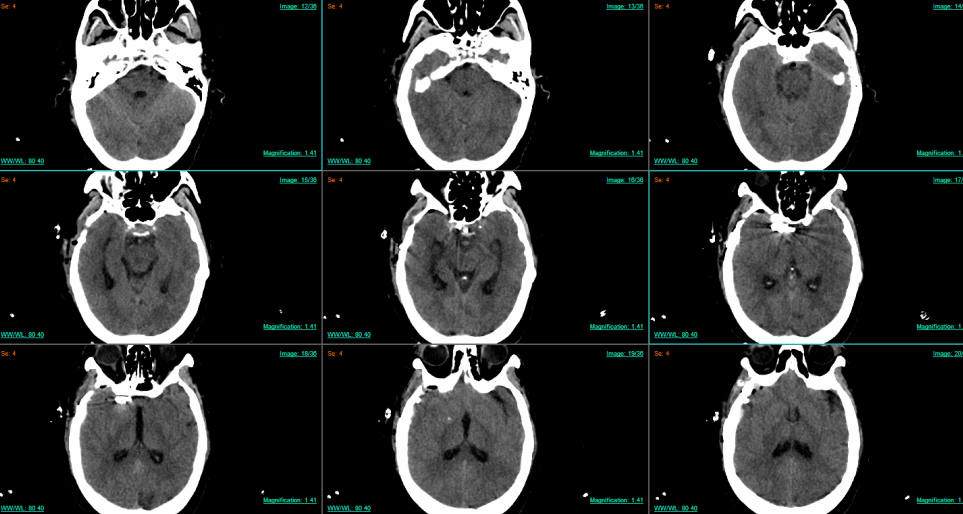

「医生,我突然头晕得厉害……」 不久前,75 岁的张奶奶被家人送进南京江北医院急诊科就诊。本以为是老年常见病,头颅 MRA 检查却给出惊人结果:右侧颈内动脉 C6 段(眼动脉段)有个瘤样凸起,疑似颅内动脉瘤。

颅内动脉瘤就像脑血管壁上吹起的 「小气球」,血流冲击下会不断变大,一旦破裂就会引发蛛网膜下腔出血,致死致残率高达 70% 以上,被称为 「颅内炸弹」。更让人揪心的是,进一步 DSA 检查发现,这颗 「炸弹」 还是分叶状的,这些分叶如同瘤体长出的 「小尾巴」,形态不规则且边界参差不齐,破裂风险极高;而左侧同一位置,竟然还有一颗 「镜像动脉瘤」。

术后 CTA 显示:动脉瘤完全消失,血管通畅无阻。这场毫米级的生命保卫战,赢了!